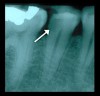

First, it is paramount for the clinician to obtain a pretreatment pulpal and periradicular diagnosis. The value of obtaining a pretreatment pulpal and periradicular diagnosis before performing restorative treatment on a carious vital tooth is that it will allow the clinician to better understand how to treat the dental pulp, especially if it is exposed during caries excavation (Figure 1). A study by Ricucci et al6 found that a clinical pulpal diagnosis of a normal pulp or reversible pulpitis had a 96.6% histologic match to the actual pulp tissue in a tooth.

Fig 1. Obtaining a pretreatment pulpal and periradicular diagnosis on tooth No. 29 before restorative treatment will allow the clinician to properly treat the dental pulp if it is exposed during caries removal.